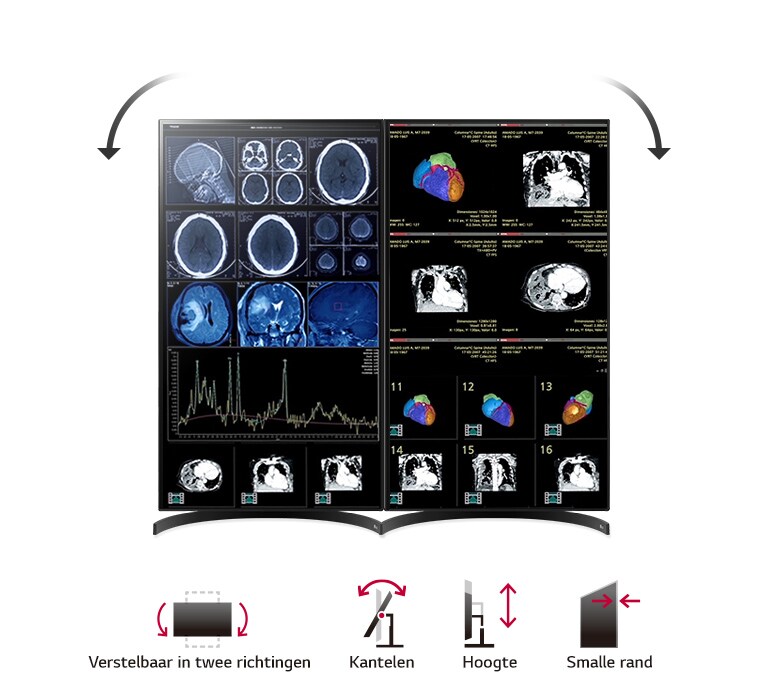

Display Position Adjustments

Tilt/Height/Pivot

Borderless Design

4-Side Virtueel Randloos Design